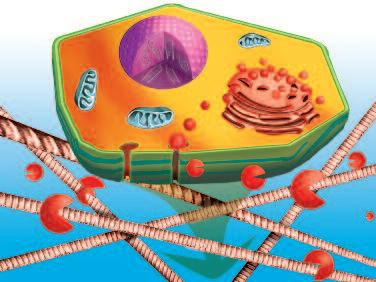

Normalmente, le cellule del nostro corpo sono inserite in una rete di collagene e di altre molecole del tessuto connettivo che le mantengono al loro posto. Affinché le cellule tumorali possano crescere, divenendo un tumore, e possano diffondersi in tutto il corpo, è necessario fendere questo isolamento del tessuto connettivo. A questo fine, ogni cellula del cancro produce ‘forbici biologiche’, ovvero degli enzimi proteolitici in grado di digerire il tessuto connettivo che circonda le cellule tumorali.

Le cellule tumorali non producono questi enzimi distruttivi solo per un breve lasso di tempo, ma durante tutta la loro esistenza. Dal momento che le cellule tumorali sono, per loro natura, immortali, un tumore in fase di crescita potrebbe essere descritto come una malattia che poco a poco digerisce il corpo dall'interno.

Una delle più importanti molecole secrete dalle cellule tumorali in grandi quantità sono gli enzimi a ‘forbice’ che digeriscono il collagene. Sono aggiunti graficamente a questa immagine, sotto forma di strutture simili ad un ‘pacman’ rosso.

Naturalmente questi sfere, nella vita reale, sono molecole biologiche, proteine, che hanno la capacità di tagliare le fibre di collagene e di altre molecole del tessuto connettivo. L‘immagine sopra mostra che non c’è un solo tipo di 'pacman' ovvero di queste molecole, ma

Digestione del tessut o connet tivo del tessuto connetti vo diversi tipi, quali il plasminogeno/plasmina e le metalloproteasi (strutture colorate tridimensionali). Queste molecole migliorano il loro effetto distruttivo attivandosi reciprocamente in forma di reazione a catena in cascata.

Nella pagina a fianco si vede la produzione di enzimi che digeriscono il collagene all'interno di una cellula (figura A). Questi enzimi vengono poi secreti nell‘ambiente di questa cellula dove ‘attaccano’ e digeriscono le fibre di collagene circostanti. Questo processo consente di creare delle ‘scappatoie’ all'interno della fitta rete di tessuto connettivo e di passarvi attraverso (figura B).

Il nucleo avvia la produzione di collagenasi

AProduzione di questi enzimi all’interno della cellula e secrezione verso l’esterno della cellula

Enzimi che divorano il collagene e i tessuti connettivi

Gli enzimi digeriscono temporaneamente il tessuto connettivo che circonda la cellula per permetterle di migrare (spostarsi) nel corpo